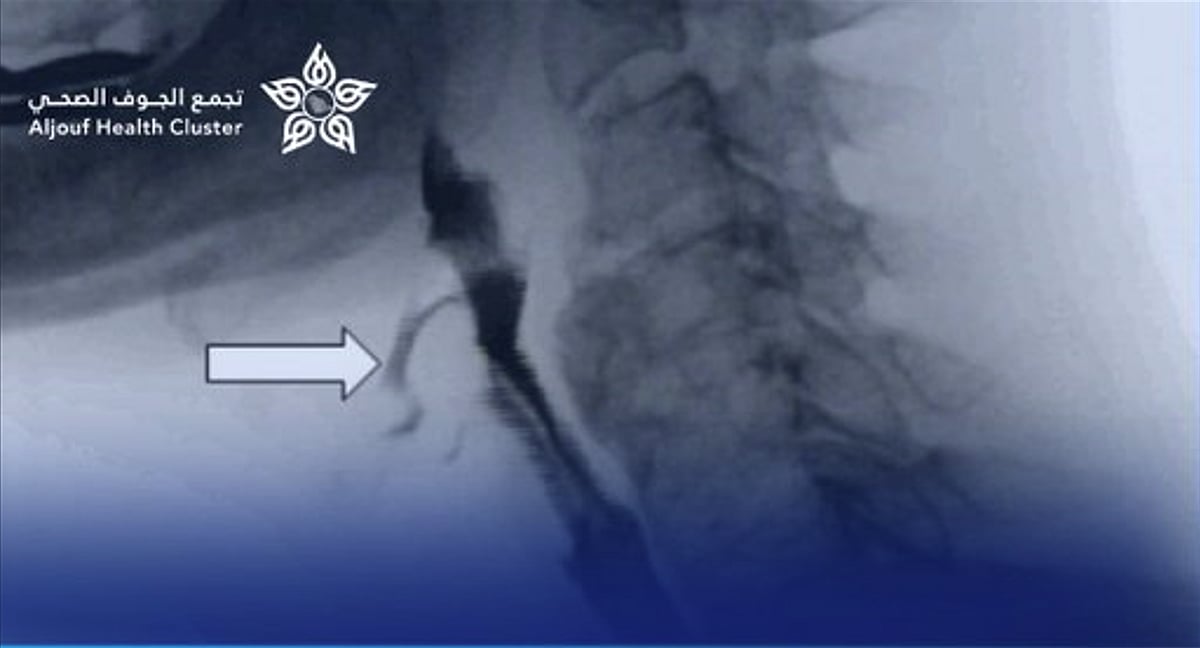

نجح فريق طبي متخصص من قسم الجهاز الهضمي للأطفال وقسم التخدير بمستشفى الملك عبد العزيز التخصصي بالجوف، بالتعاون مع مستشفى النساء والولادة والأطفال، في إجراء عملية توسيع للمريء بالمنظار لطفل يبلغ من العمر 11 عامًا، دون الحاجة إلى أي تدخل جراحي.